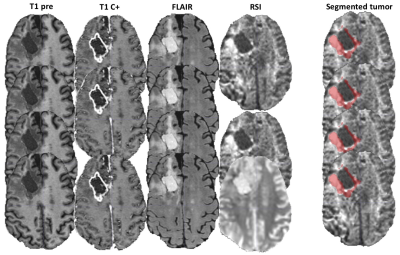

An example of segmentation for a cellular non-enhancing tumor case is shown in Fig 1. While the regions of FLAIR hyperintensity in the splenium of the corpus callosum and bilateral parieto-occipital white matter did not demonstrate significant enhancement, they showed increased RSI cellularity signal compatible with cellular infiltrative tumor (Fig 1A). These regions were segmented as tumor tissue in Fig 1B. An example of segmentation for a case with only post-treatment changes is shown in Fig. 2. The red arrow in Fig 2A demonstrated peripheral nodular enhancement at the anterior margin of the surgical cavity but the RSI cellularity map (blue arrow) did not demonstrate RSI cellularity signal in the enhancing regions or surrounding edematous tissue, suggesting post-treatment changes rather than recurrent tumor. This was confirmed on the follow-up scan (Fig 2B) where this region of nodular enhancement improved (green arrow) and tissue necrosis increased (yellow arrow) as shown by the very high RSI signal. Tumor segmentations with several variations of the Deep Learning model with different inputs are shown in Fig 3 for an individual test subject and the average Dice scores over the entire testing set is shown in Table 1. Adding RSI cellularity to the combination of T1 pre, T1C+ and FLAIR sequences increased the Dice score from 0.50 to 0.65. Although adding ADC to T1, T1C+, and FLAIR sequences also increased the Dice score, the increase was less pronounced than with RSI (0.60 ± 0.31 vs. 0.65 ± 0.24)." Fig 4 demonstrates an inverse relationship between volume of enhancing cellular tumor (both T1C+ and RSI positive) and the overall survival for patients with RSI scans within 180 days following surgical resection (n=20).

Fig. 1. Example of segmentation for a cellular non-enhancing tumor case. A) MRI volumes. While the hyper FLAIR signal regions in the splenium of the corpus callosum and bilateral parieto-occipital white matter did not demonstrated enhancement, they showed increased RSI signal demonstrating residual tumor. B) These regions were included in manual segmentations of cellular tumor.